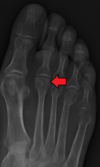

Grey Turner’s sign

Flank ecchymosis

Acute pancreatitis